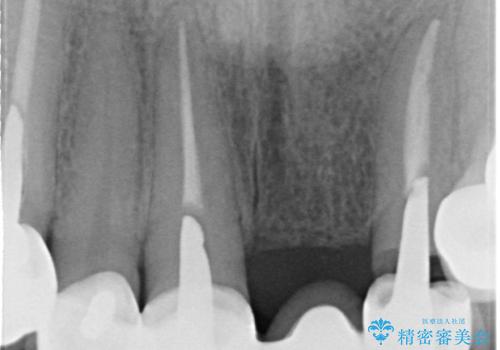

歯肉縁下カリエスも認められるため、挺出を行いセラミックブリッジを審美的に新製します。

挺出について

虫歯が深くなった場合、挺出や歯周外科を行い歯周組織の状態を改善することでより安定した状態で予知性の高いセラミックブリッジを製作することが可能となります。